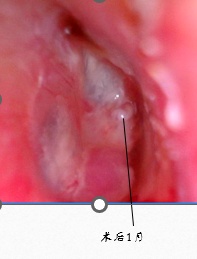

术后1月小丽来复查,通过耳内镜检查看到之前的鼓膜穿孔已经完全愈合,听力也完全恢复,她又可以在泳池里畅快的游泳了。